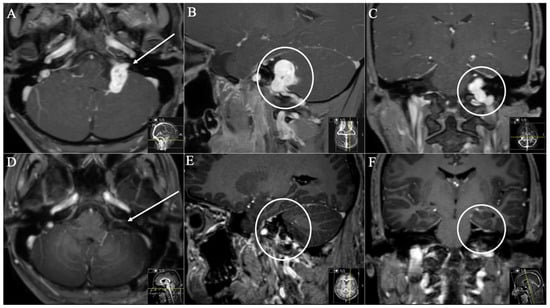

3. Results

3.1. Patient Population

3.2. Postoperative Outcome